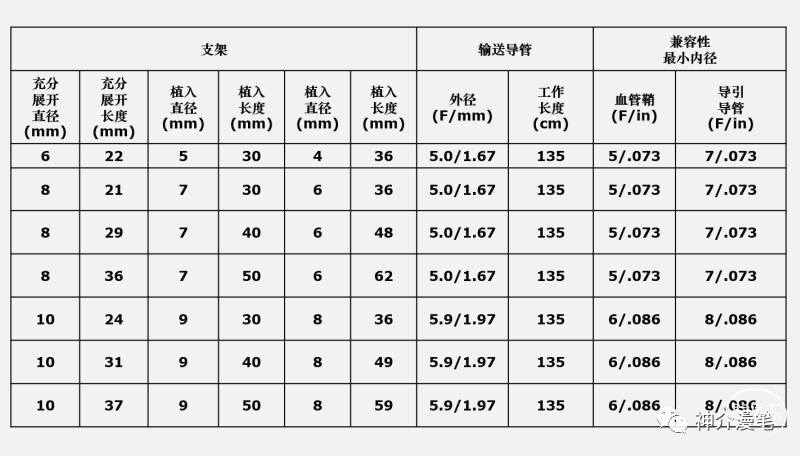

需要提醒大家注意的是,编织支架在不同管径的血管中会出现明显长度的变化,如下表所示。因此选择支架长度时一定要根据目标血管直径来选择合适长度的支架,避免过长或过短,另外wallstent支架释放后会有一定程度的回缩,所以定位支架着陆点时应预留足够测长度,防止支架短缩后无法完全覆盖狭窄造成尴尬的局面。另外需要注意的是,wallstent支架和所有闭环支架一样,在释放时需远端打开一定长度后方能彻底打开贴壁,在此过程中如后手把持的力度不够有可能造成支架下滑。

雅培上面两款支架一个开环,一个闭环,应用的场景,使用原则和上诉所说的支架大体差不多,大家可以再看一下他们的具体型号和尺寸。酌情使用,比较有意思的是这两款支架的释放都是“半自动化的”,支架到位后通过旋转释放手柄或回拉把手即可完成。不需要前面几款支架的推扒技术,所以一旦支架到位良好,释放极度简单,几乎就是傻瓜式释放,特别适合新手小白使用。

3-6的支架可以使用4F鞘或6Fguiding进行释放,下图为其常见支架型号。

最后来一个汇总图吧,把所有支架的参数放在一起,大家一块比一比,这样心中就都有数了。